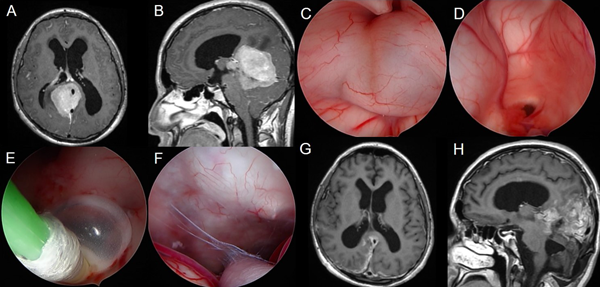

Se presentan en figuras 8 a 12 los casos ilustrativos más representativos de nuestra serie.

Figura 8: Hidrocefalia en contexto de germinoma gigante supra e infratentorial: A-B) RM preoperatoria. C-F) Hallazgos intra-operatorios. G-H) RM cerebral postoperatoria.